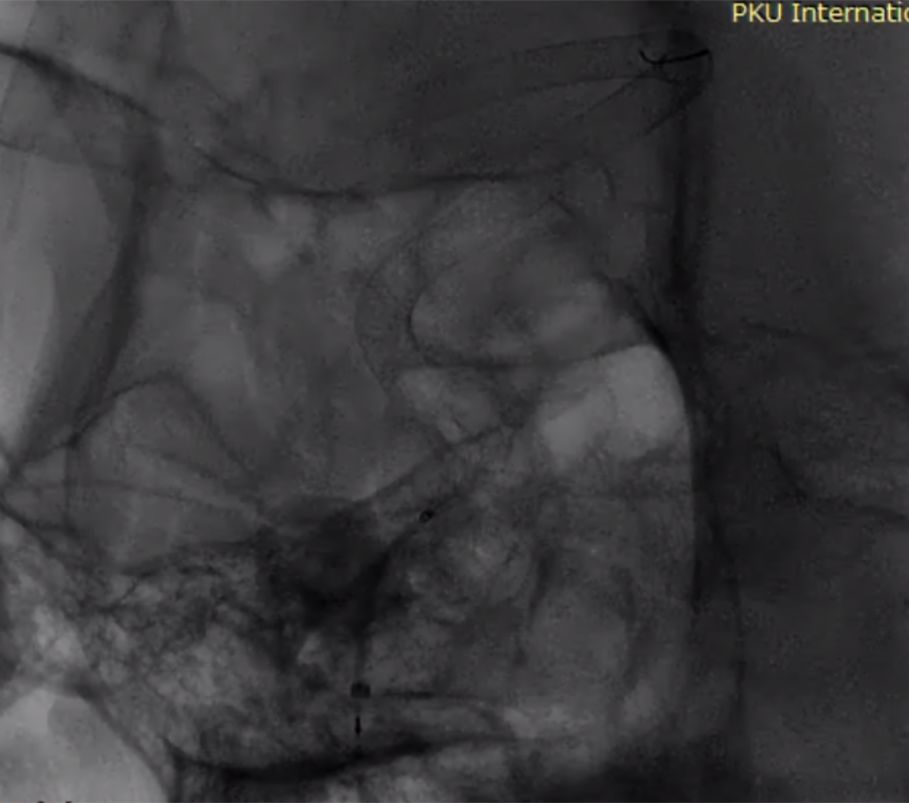

术后复查影像(图11)。

图11

本例介入手术共使用4枚长密网支架桥接放置治疗巨大长夹层动脉瘤,手术顺利,术中清晰可见支架桥接与放置打开情况,微创介入手术大约一个多小时,术后三天患者无任何后遗症步行出院,患者术后半年CTA血管造影复查,脑动脉瘤顽疾得以治愈,脑血管形态已经基本恢复正常 ,患者恢复良好,生活完全正常并重返工作岗位。